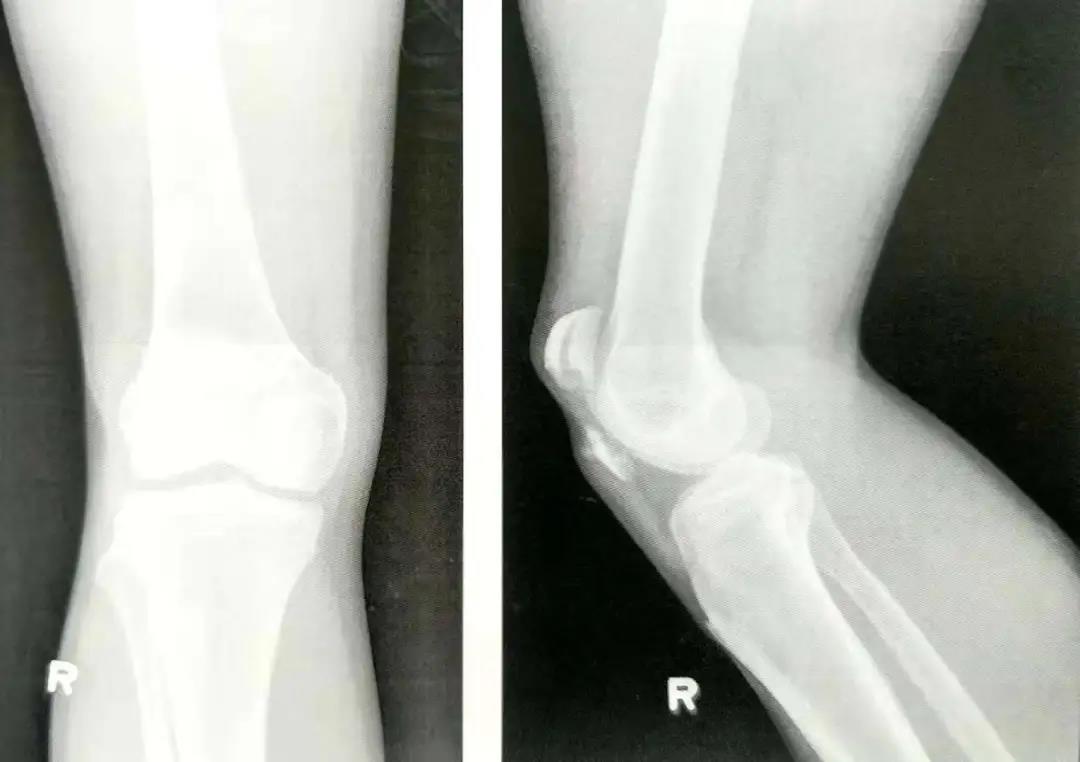

- 在穿过骨折线之前,可用术中透视(正位和侧位)直视下或将手指伸到髌骨下触摸的方式来确保骨折已复位。

- 在关闭伤口前用术中透视或X线评估骨折复位和内置物的位置情况。